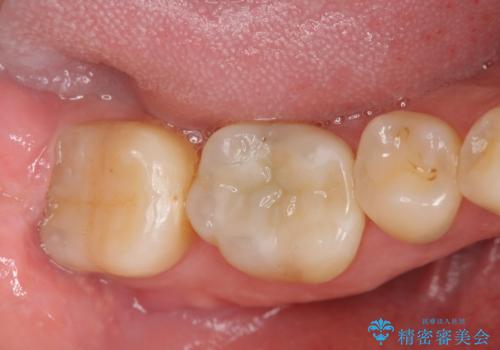

現在入っている銀歯を丁寧に除去し、適合の良い精密なセラミックインレーによる修復を行います。

- 16万円(セラミックインレー×2)費用は治療当時の料金となります

下顎の銀歯はよく見えるのでセラミックに置き替えると見た目の改善が顕著です。